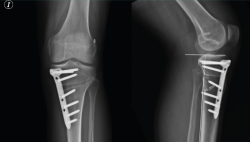

Figura 9. Fijación de la placa con tornillos. Se señala con la flecha la ausencia del tornillo más anterior, dada su coincidencia con el túnel tibial.

Figura 10. Radiografía de control a los 3 meses en proyecciones anteroposterior y lateral. En la proyección lateral se aprecia que no se modifica la pendiente tibial posterior tras la osteotomía tibial alta de apertura medial.